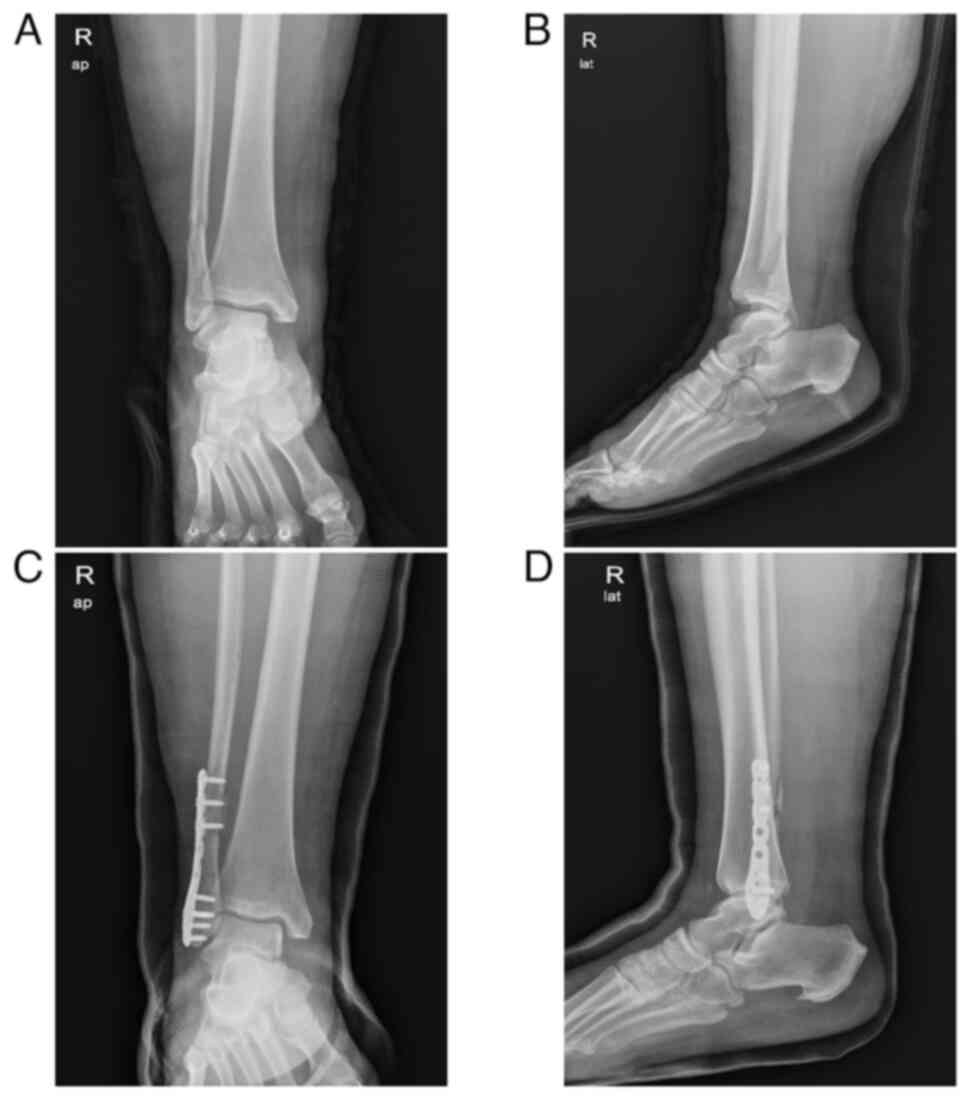

A 36-year-old, virgin woman, presented to the emergency department of another institution with right ankle pain due to a fall caused by dizziness and headache after menstruation. The initial evaluation revealed swelling of the right ankle. Initial radiography revealed a right ankle fracture without dislocation. The patient was hypertensive, with a heart rate of 102 beats/min. Initial laboratory results showed a severely low hemoglobin level (4.9 g/dl, reference range, 12.0-16.0 g/dl) and hematocrit (16.6%, reference range 36.0-46.0%). She was treated with packed red blood cells and iron infusion. Her weight and height were 95.0 kg and 162 cm, respectively, and her body mass index (BMI) was 36.2 kg/m2. She had a recent history of menorrhagia and irregular cycles that lasted for two years. She had never presented to a doctor because of her symptoms. The patient was transferred to the Pusan National University Hospital (Busan, Korea) and evaluated by an orthopedic surgery team (Fig. 1). The decision was made to proceed with the surgical intervention. During the evaluation, she was referred to the gynecology oncology unit for further workup after a computed tomography (CT) scan revealed a significant endometrial mass suspected to be EC. Magnetic resonance imaging (MRI) of the pelvis revealed a 6.7-cm-sized endometrial mass with restricted diffusion, myometrial invasion of <1/2, and bilateral polycystic ovaries. She had been receiving antihypertensive drugs for two years but had recently stopped taking them because she experienced hypotension caused by the drug. Her family history included hypertension in her father and elder brother. Endometrial pipelle sampling revealed FIGO grade 2 endometrioid adenocarcinoma. Positron emission tomography-CT showed no evidence of metastases.

Figure 1

Radiological findings. (A and B) Preoperative AP and lateral X-ray view of the patient's right ankle showing a distal fibular fracture and a posterior malleolar fracture. (C and D) Postoperative AP and lateral X-ray view of the right ankle fracture treated with a plate and screws showing good bony healing. AP, anteroposterior.

Laboratory findings including fasting blood sugar, HbA1c, C-reactive protein and CA125 levels, were unremarkable. First, the patient underwent open reduction and internal fixation involving screw fixation for a right ankle syndesmosis injury, distal fibular fracture, and ankle posterior malleolar fracture. The postoperative follow-up showed successful healing and functional recovery (Fig. 1). A total of 4 weeks later, robot-assisted total hysterectomy, bilateral salpingectomy and sentinel lymph node sampling were performed. Final pathology revealed stage 1B, grade 2 endometroid adenocarcinoma with substantial lymphovascular space invasion (LVSI) (Fig. 2). Regional lymph node involvement was not identified. The peritoneal fluid cytology was negative for malignant cells. Immunohistochemistry staining revealed p53 (-), MLH1 (+), PMS2 (+), MSH-2 (+) and MSH-6 (+). The patient received 50.4 Gy external beam radiotherapy (EBRT) to the whole pelvis. Chest and abdominopelvic imaging (CT or MRI) were checked every 6 months. The 26-month postoperative follow-up showed that the patient was disease-free. The present study was reviewed and approved by the Institutional Review Board of Pusan National University Hospital (approval no. 2404-017-138; Busan, Korea). Written informed consent was obtained from the patient for publication of data of her medical case and associated images.